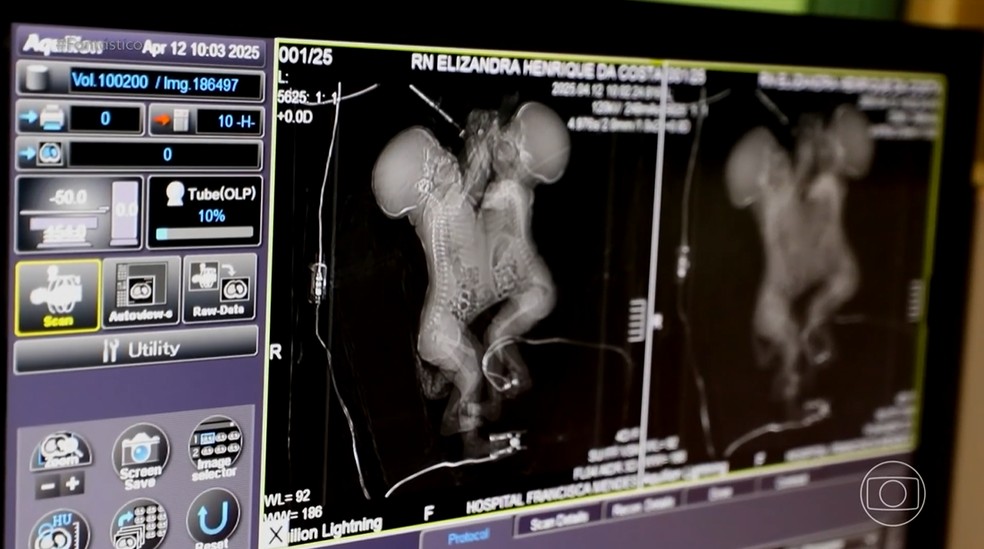

Elizandra descobriu a gravidez em julho de 2024, mas ela e o marido, Marcos Oliveira, celebraram, preocupados, a notícia: os exames mostraram que as bebês estavam unidas pelo tórax e abdômen. Uma situação complicada para a cidade do interior paraense onde moravam.

As meninas compartilhavam o fígado, o pericárdio e até a cavidade cardíaca. Os médicos dividiram os órgãos e separaram os ossos do tórax. A cirurgia foi considerada um sucesso. “Nunca perdi a fé de que elas iam sair com vida do centro cirúrgico e bem recuperadas”, afirmou a mãe, emocionada.